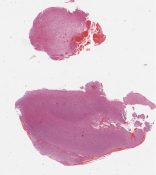

CANP2008-6.svs

18000 x 21609

@ 20X